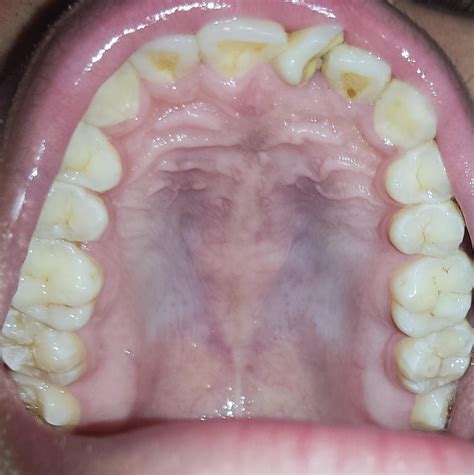

Exploring the intricacies of the roof of mouth, also known as the palate, reveals a fascinating world of anatomy and function. The roof of mouth plays a crucial role in various physiological processes, including speech, swallowing, and respiration. Understanding its structure and function can provide valuable insights into oral health and overall well-being.

The roof of mouth is composed of two main parts: the hard palate and the soft palate. The hard palate is the anterior portion, which is bony and covered by a mucous membrane. It provides structural support and is essential for the formation of certain speech sounds. The soft palate, on the other hand, is the posterior, muscular portion that helps in closing off the nasal cavity during swallowing and speech.